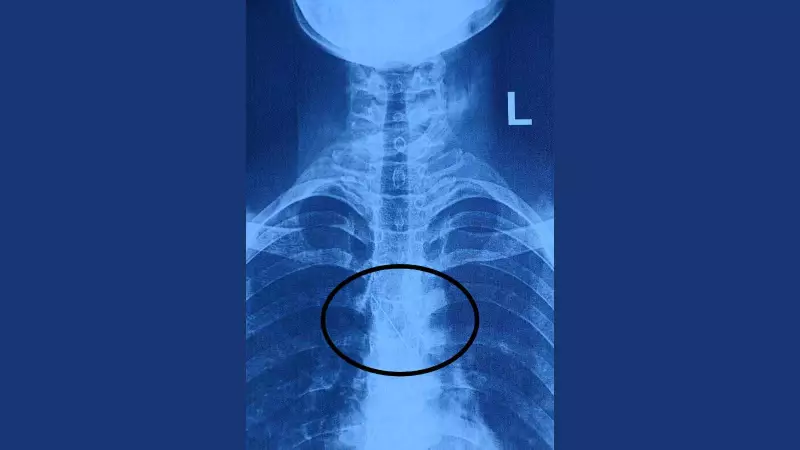

Her family rushed her to the emergency department of SSG Hospital within an hour. An urgent X-ray revealed the gravity of the situation: the metallic pin was lodged in her left main bronchus, positioned dangerously close to her heart. This required immediate medical intervention to prevent potentially life-threatening damage to her lungs or heart.

The hospital confirmed that the pin was found in the left main bronchus, impinging on the right wall of the trachea. Following the operation, the girl was monitored and was discharged on Wednesday morning, free from any dangerous respiratory complications.